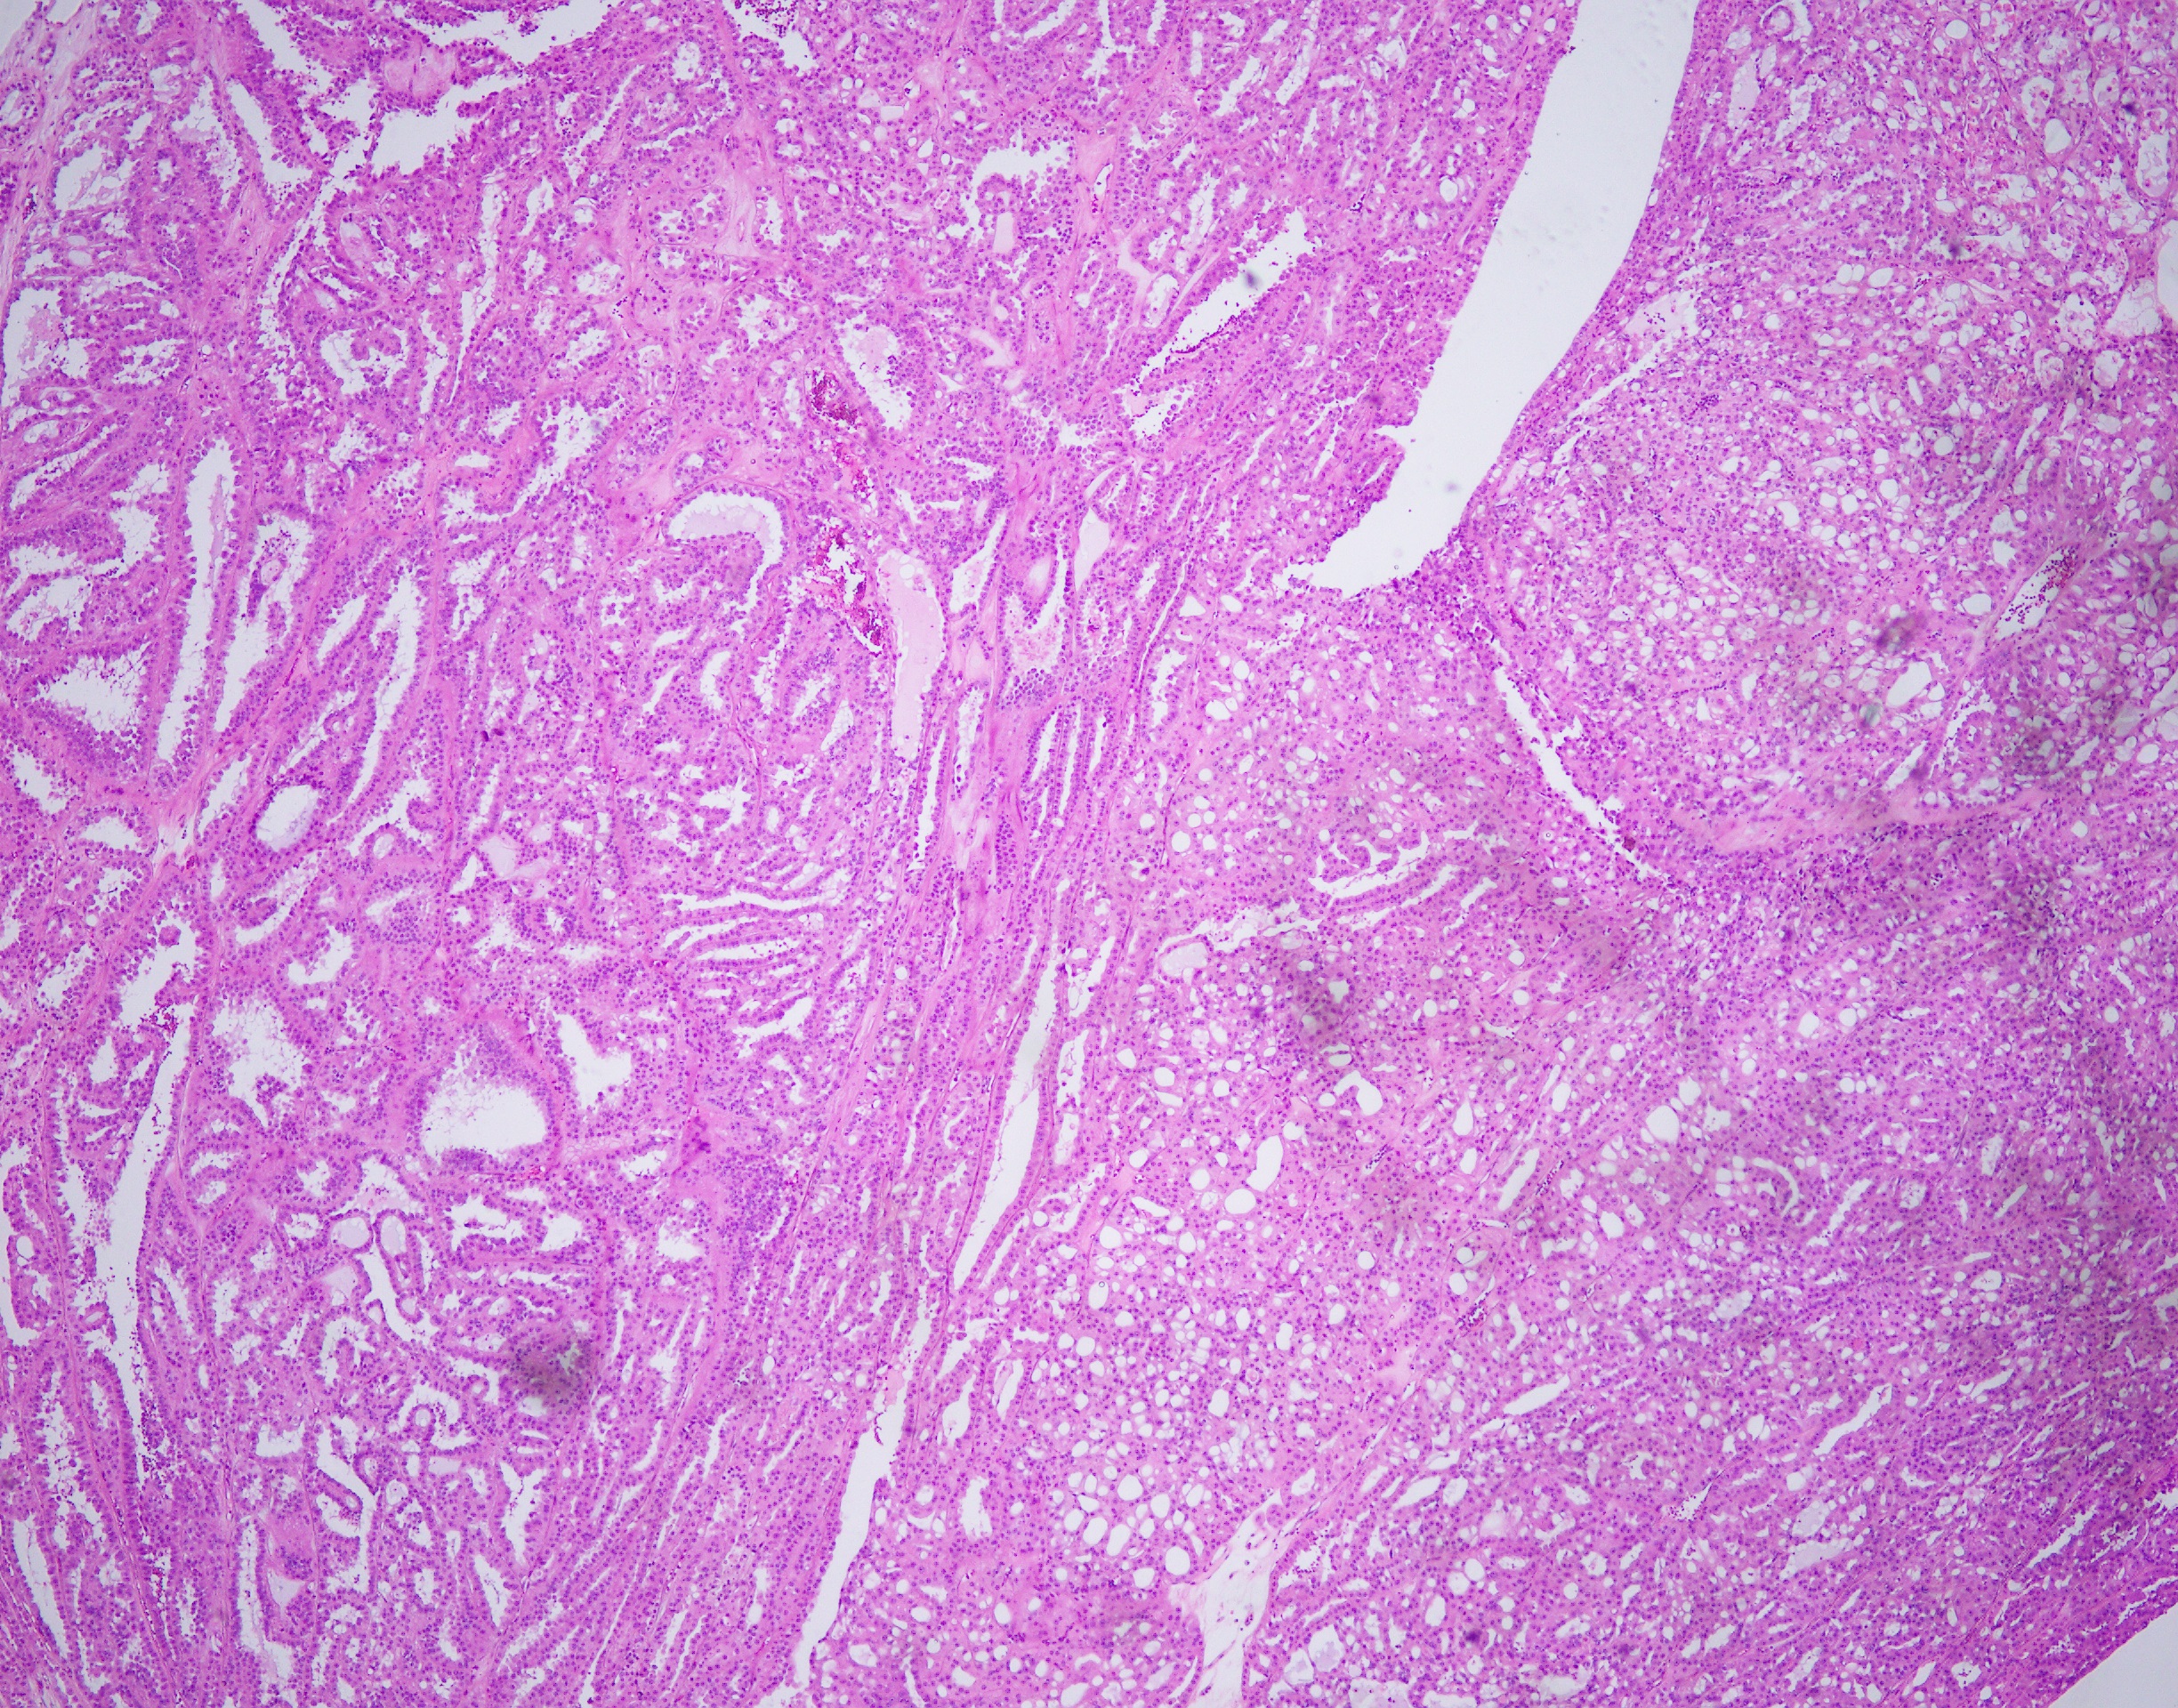

35 year-old-male with an 8 cm well-circumscribed, solid mass located in the upper pole of the left kidney with associated para-aortic metastasis. H&E, and IHC stains are shown.

Histologically, FH-deficient RCCs were originally described as type 2 papillary RCC and occasionally as collecting duct carcinoma (CDC), with a spectrum of architectural patterns including papillary, tubulopapillary, tubular, cribriform, solid and cystic elements. The morphological hallmarks of HLRCC are characteristic nuclear features: a large nucleus with a very prominent inclusion-like eosinophilic nucleolus surrounded by a perinucleolar halo. Based on these architectural and nuclear features, the differential diagnosis of HLRCC could include a variety of high-grade RCCs of different histological subtypes, particularly type 2 papillary RCC, CDC, or high-grade RCC, unclassified. Recently, an expanded histological spectrum of FH-deficient RCC has been described, including tubulocystic carcinoma with poorly differentiated foci, and SDH-deficient RCC like morphology was observed in FH-deficient RCC.